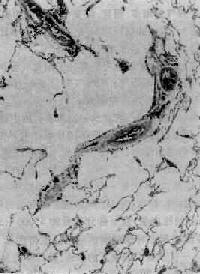

腺泡中央型肺气肿

图9-12 腺泡中央型肺气肿

呼吸细支气管呈囊状扩张,伴行肺动脉(径80μm)管壁增厚,其分支内膜增厚,管腔极度狭窄